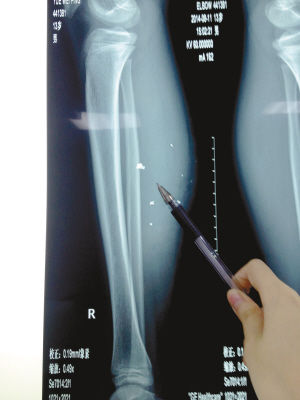

X光片顯示:手機電池內(nèi)的物質(zhì)被炸進了小平的右小腿里

8月10日凌晨,小平轉(zhuǎn)院至重慶醫(yī)科大學(xué)附屬兒童醫(yī)院。小平的主治醫(yī)生骨科二病房周悅航醫(yī)生介紹,入院時小平右小腿腫脹,經(jīng)檢查,發(fā)現(xiàn)有爆炸傷伴異物殘留。傷口較深,約1.5厘米~2厘米,手機爆炸后進入患兒小腿的異物約有10處。周悅航說,由于進入皮膚的異物較多,已深入肌肉,且比較分散,最深的一塊貼近骨頭,可能需要多次手術(shù)。

另外,醫(yī)生擔心手機爆炸后金屬物進入患兒體內(nèi)可能會對患兒肌肉造成損傷,所以需盡快手術(shù)。據(jù)悉,8月14日上午,小平將接受小腿爆炸傷清創(chuàng)與異物取出術(shù)。